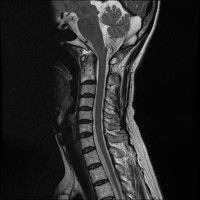

목,허리 디스크 엠알 판독.....

경추 요추 디스크 둘다 있는 상태고 경추몇번에서 몇번사이 요추몇번에서 몇번사이인지 알려주세요

목

• 1번 째 사진